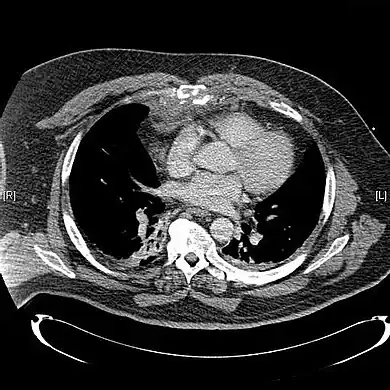

CT scan showing a comminuted sternal fracture.[14]